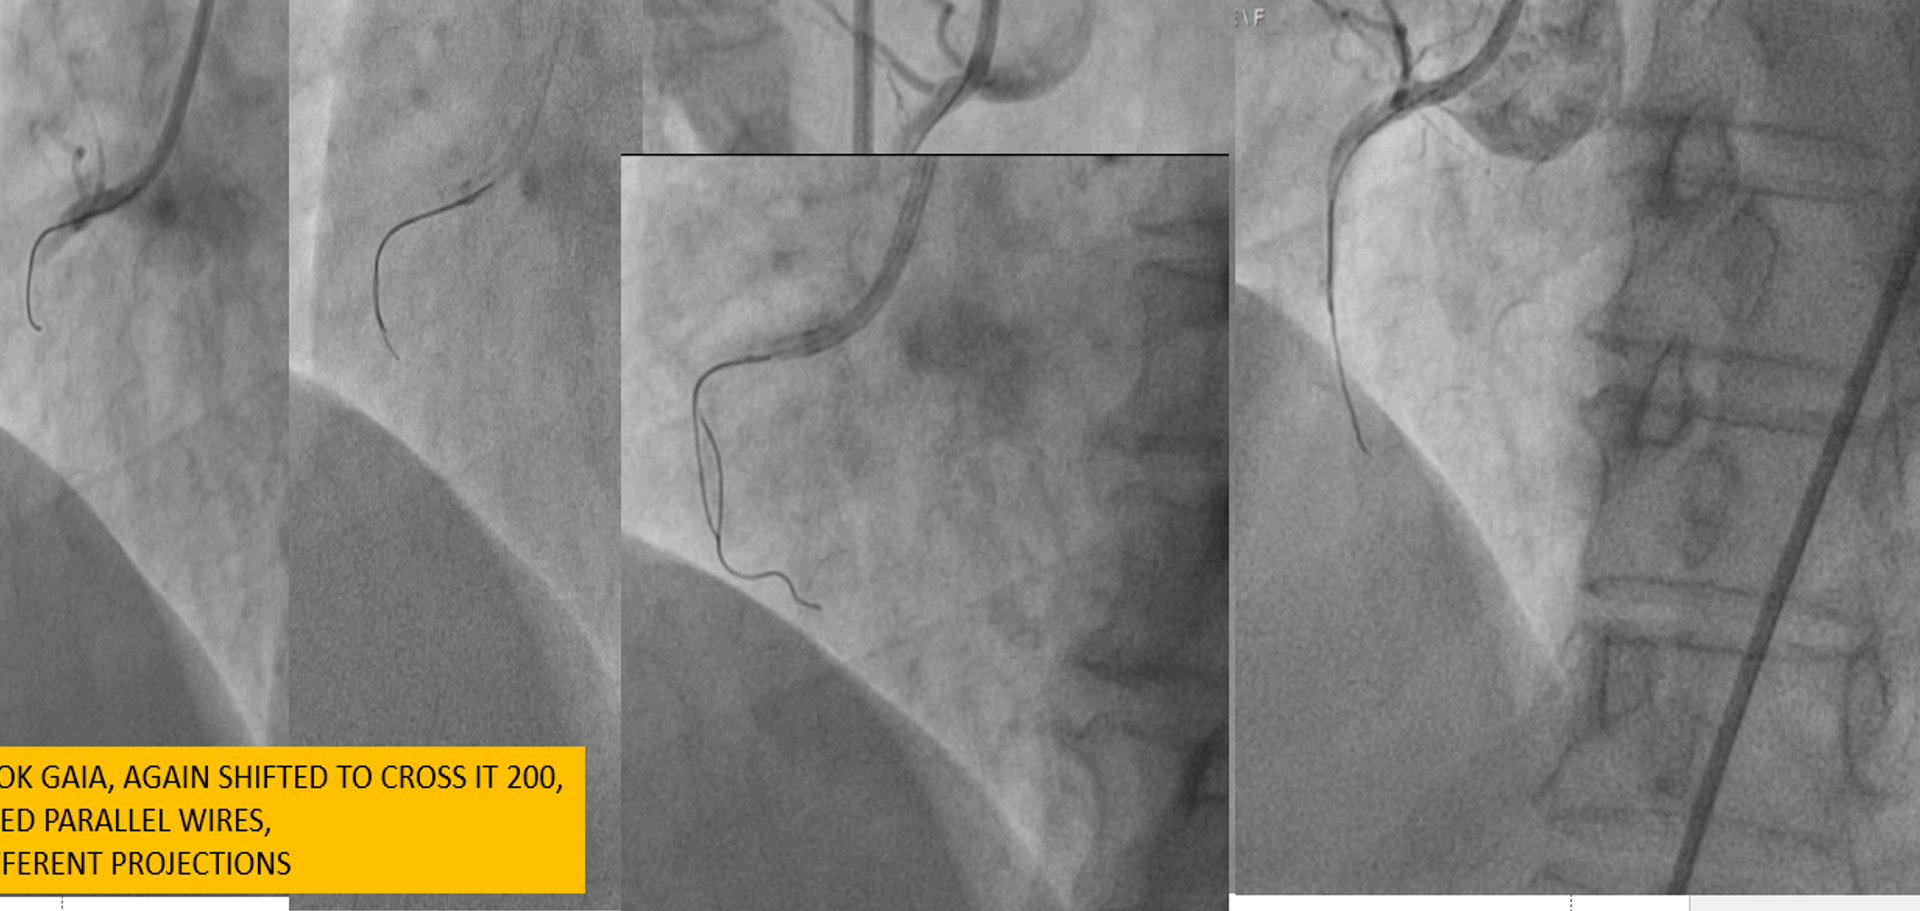

PTCA with Retrograde Rendezvous for Chronic Total Occlusion (CTO)An individual with a stubborn Chronic Total Occlusion (CTO) in the RCA (Right Coronary Artery) initially underwent a failed antegrade percutaneous transluminal coronary angioplasty (PTCA). Despite multiple wire attempts (e.g., CROSSIT 200, PILOT 150), the procedure was aborted due to a spiral dissection.A month later, a second attempt was made using a more advanced approach. The steps were as follows:Retrograde Access: The interventional team chose a retrograde approach, navigating a wire and microcatheter through collateral vessels to reach the RCA distal to the blockage.Antegrade Access: Simultaneously, an antegrade wire was advanced from the proximal end of the RCA to the blockage site.Rendezvous: The retrograde and antegrade wires were "kissed" at the site of the CTO. This crucial step, known as the rendezvous technique, allowed the antegrade wire to be precisely guided.Final Crossing: The antegrade wire was then advanced through the antegrade microcatheter, alongside the retrograde wire, finally penetrating the true lumen distal to the CTO.Revascularisation: Once the path was clear, the retrograde wire was removed. The RCA was then successfully revascularized with balloon dilations and the deployment of two stents.

RETROGRADE WITH GRADE 1 OR 2 COLLATERALLS IS CHALLENGINGWhen a microcatheter can not cross RETROGRADELY INTO THE RECIPIENT VESSEL, THERE IS DIFFICULTY TO CROSS the CTO SEGMENTHYBRID APPROACH AND TECHNIQUES LIKE RENDEVOUZ ARE VERY EFFECTIVE